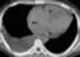

Myxoma of right ventricle

A myxoma (New Latin from Greek 'muxa' for mucus) is a myxoid tumor of primitive connective tissue. It is most commonly found in the heart (and is the most common primary tumor of the heart in adults) but can also occur in other locations. [Source: Wikipedia ]